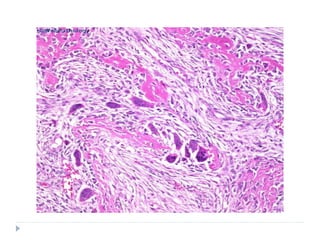

HISTOPATHOLOGY

 SIMILAR HISTOPATHOLOGIC APPEARANCE IS SEEN IN ALL

THE CLINICAL TYPES

 Kaposi’s sarcoma evolves through 3 stages

 Patch stage

 Plaque stage

 Nodular stage

 Patch stage:

 Proliferation of small veins and capillaries around pre-

existing dilated vessels

 Slit-like vessels are seen which are lined by plump, mildly

atypical endothelial cells

 Scattered erythrocytes and hemosiderin deposits are

seen

 Perivascular spindle cell proliferation with minimal cellular

atypia

 Plaque type

 Increased number of small capillaries and dilated vascular

channels

 Slit-like vascular channels without visible endothelial

lining

 Large number of extravasated RBCs and abundant

hemosiderin deposits

 Proliferating sheets of sarcomatous or atypical spindle

cells

 Lesional cells have enlarged hyperchromatic nuclei with

mild to moderate pleomorphism

 Minimal mitotic activity

 Spindle cells increase to form nodular tumour-like mass